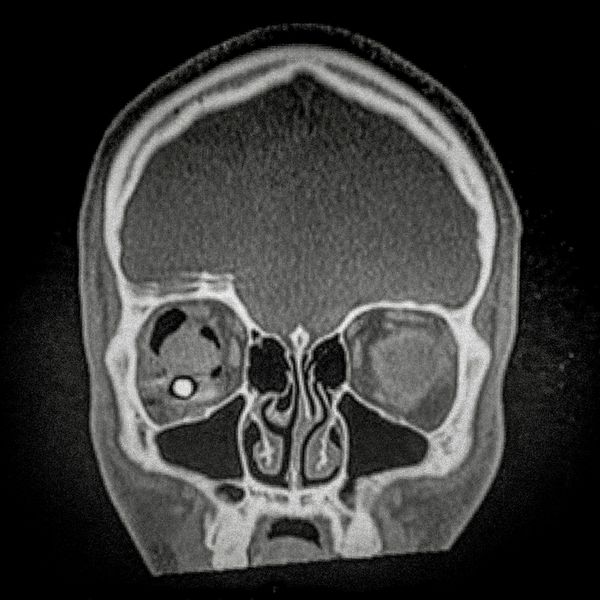

460 people have been seriously injured in their eyes, 34 of whom suffered total loss due to the indiscriminate use of pellets and tear gas bombs by the Carabineros de Chile special forces. The Carabin

460 people have been seriously injured in their eyes, 34 of whom suffered total loss due to the indiscriminate use of pellets and tear gas bombs by the Carabineros de Chile special forces. The Carabineros fired their rubber bullets and tear gas guns directly into the faces of the protesters during the Chilean social outbreak between late 2019 and early 2020. This figure has made Chile the country with the world record for eye mutilation by state and security forces.

By early March 2020, around 3,838 people had been injured and according to the Chilean Society of Ophthalmologists and human rights organizations, 460 of them ended up with serious eye complications, loss of the eyeball, and also loss of sight. This figure has made Chile a world record for eye mutilation, due to the indiscriminate use of pellets and tear gas bombs by special forces of the Carabineros, who have shot their weapons directly into the faces of the protesters.